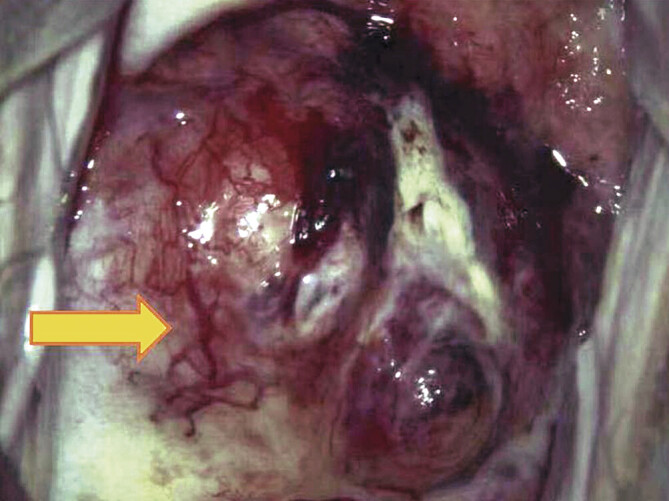

Abstract Image